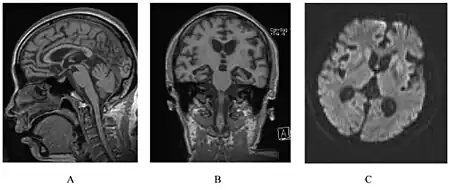

| a) Examination of the brain showing cortical brain atrophy b) coronal slide demonstrating severe cortical and subcortical atrophy c,d) microscopic anatomopathological analysis of the brain | |

It results in cerebellar atrophy and can be identified through genetic testing.[9] If the genetic mutation is present, GSS will eventually develop.